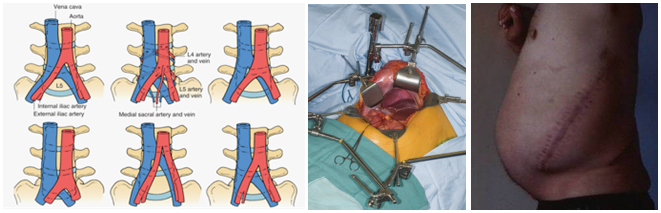

然而,采用传统开放手术的一些弊端逐渐浮现,如腹壁不对称、切口疝、不美观;牵开复杂的大血管时易损伤(1-24%);上腹下丛损伤-逆向射精(4%);附加后路内固定增加手术创伤和费用,影响了人们对开展该技术的热情[9]。

正是由于以上问题,使得人们在开展该技术上存有疑虑并限制了发展,并被打上了“昙花一现”的标签。因此,在1997年,Mayer提出了小切口经肌间、腰大肌-血管自然间隙入路进行腰椎前路手术的新理念[12]。该技术在L2-S1均可采用,L4/5以上腹外侧入路,L5/S1采用下腹入路,手术创伤较传统入路明显减少,但仍然避免不了腹部大血管损伤的问题。

笔者及团队自1998年起开展了腹腔镜下腰椎融合技术,该技术可以说是现代OLIF技术的全内镜下的“版本”。然而,在临床应用过程中,腹腔镜锁孔下操作存在着上述诸多问题,为兼顾微创的同时改善手术的便利性与实用性,2002年起,腰椎前路融合手术均革新为腹腔镜辅助小切口或单纯小切口方式进行。在融合器稳定性方面,由于早期缺乏自稳装置,前路术后往往需要进行后路补充固定。近年来,随着理念的进步和经验积累,涌现了附有自身稳定的融合器如LDR等。为此,结合自锁cage的应用,于2015年设计了腹前外侧入路腰椎间融合(ALLIF)技术,该入路设计简单、直接、安全。术中患者采用斜卧位,切口根据椎间隙的体表投影,贴腹直肌左外缘作4-6cm横/斜切口所经层次:腹外斜肌-腹内斜肌-腹横肌至腹膜外间隙,用常规腹部拉钩将血管及腹膜稍牵向内侧,另一拉钩置于椎体侧前、交感神经链前方,将其稍向后牵开。辅以头灯放大镜或显微镜,直接对神经结构进行减压,选用自锁型融合器,不需附加前路钉板或后路钉棒,同时对于退行性滑脱的病例,采用前侧入路方式可以获得有效的椎体复位,从而达到减压、复位、融合与稳定等“四位一体”,“一箭多雕”之目的[16,17]。